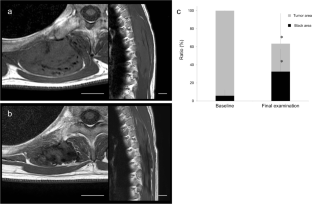

Results

PFS was significantly higher in cases with BFS than without BFS on T1WI (p < 0.01), but there was no significant difference in PFS between cases with and without BFS on T2WI. Multivariable Cox proportional hazards analysis revealed that the absence of BFS on T1WI was a high-risk factor for progression (hazard ratio, 14.9; p < 0.01). Drastic tumor regression was apparent with significantly increased low-signal area in cases with BFS on T1WI. Intra- and interobserver reliabilities of BFS on T1WI were in almost-perfect agreement (κ > 0.8).